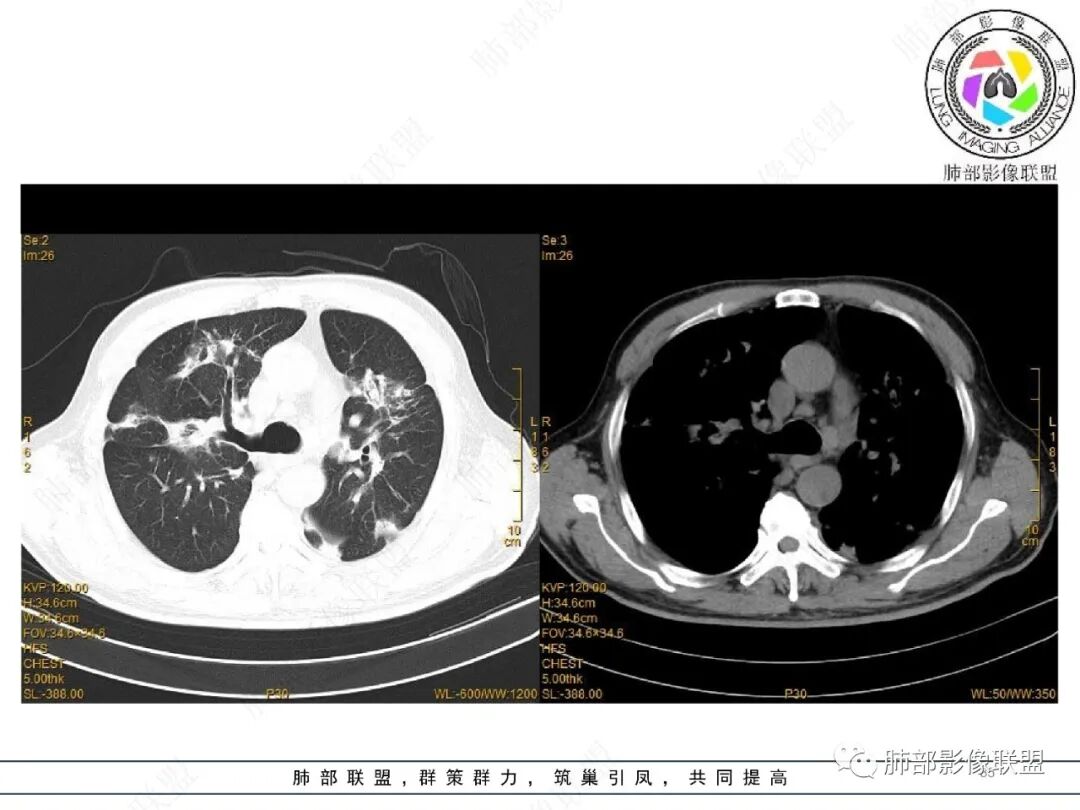

65岁男性。2022.2.17因声音嘶哑入院检查发现肺部病变,未规范治疗出院。2022.4.10因胃出血急诊入院,病情稳定后有咳嗽转入呼吸科治疗,无咳痰、无发热、无呼吸困难。白细胞、中性粒细胞轻度升高,血沉升高,抗髓过氧化物酶抗体IgG阳性,余实验室检查(-)。

2022.2.17CT显示两肺中内带多发结节影、斑片影、条索影,部分病灶侧向融合与胸膜平行。部分病灶沿着支气管血管束分布、其内支气管稍扩张。部分病灶呈反晕征。大部分病灶边界显示清晰,部分病灶周围可见边界不清的GGO。2022.4.12CT显示两肺中内带多发结节影、条索状、条带状高密度影,边界收缩平直凹陷,大部分病灶沿着支气管血管束分布,亦有位于胸膜下侧向融合与胸膜平行的病灶。总体与第一次CT对比两肺病灶明显吸收。